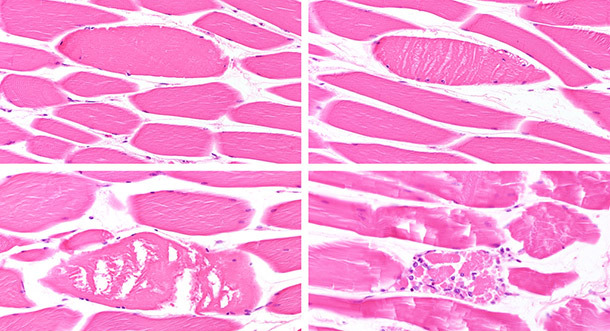

Les deux cadavres présentaient une bonne condition corporelle et de la cyanose prononcée sur la zone ventrale de l’abdomen et le cou. Les muscles squelettiques, particulièrement le M longissimus dorsi et le M semimembranosus, ont montré des zones pâles, peu flexibles et friables (figure 1). Le myocarde des deux truies avait aussi des altérations blanchâtres localisées (figure 2). De plus, il y avait des pétéchies subépicardiques multifocales. Sur l’une des truies on a aussi observé une pleurésie fibrineuse locale légère ainsi que des nodules nécrotiques totalement encapsulés dans les deux lobes diaphragmatiques du poumon. L’estomac des deux truies contenait de l’aliment sec. On n’a pas trouvé de lésions pathologiques dans la cavité abdominale, dans les intestins, le foie, la rate, les reins, la vessie, le cerveau ni les os.

Figure 2: Altérations blanchâtres localisées du myocarde

On a détecté A. pleuropneumoniae dans le tissu pulmonaire nécrotique et dans les bronches par culture bactérienne. L’échantillon de tissu pulmonaire sans altérations pathologique a été négatif aux bactéries pathogènes. Dans les échantillons de muscle squelettique et de myocarde fixés dans le formol, on n’a pas trouvé de lésions microscopiques qui confirmeraient la suspicion de déficience de vitamine E/Sélénium.

Dans le second examen histologique des échantillons de muscle squelettique, les chercheurs de l’institut vétérinaire pathologique et légal ont observé des altérations dans les cellules musculaires isolées qui présentaient différentes étapes de dégénérescence des fibres musculaires. Certaines étaient gonflées et présentaient une perte de striation. D’autres parties des muscles montraient des signes de nécrose aigue des fibres musculaires (figure 3). Les observations microscopiques du myocarde coïncidaient avec un trouble cardiaque aigu. Ces résultats ont confirmé les découvertes macroscopiques caractérisées par la pâleur des muscles et des fibres peu flexibles et friables qui ont levé les suspicions de dégénérescence musculaire nutritionnelle principalement due à un manque de vitamine E/Sélénium.

Figure 3 : différentes étapes de dégénérescence/nécrose des fibres musculaires (de la tuméfaction modérée avec perte de striation à la désintégration complète et début de réabsorption). BAR = 80µm